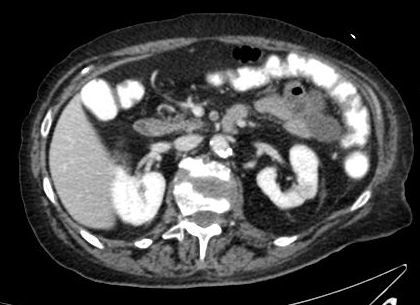

TDM réalisé dans le cadre d’un syndrome occlusif (avec vomissements précoces, météorisme discret, douleurs ++) = niveau grêlique plutôt

iléus biliaire. Probable cholécystite négligée auparavant avec création fistule biliaire